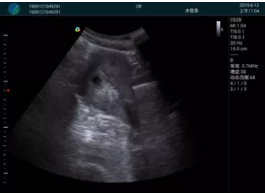

清晰顯示孕囊,通過軟件包計算孕齡7w+6d

M20實時引導,術中清晰顯示孕囊被破壞和抽吸針的過程,清晰顯示吸引針

抽吸結束后縱切子宮,孕囊已被完全抽吸,未見明顯殘留

橫切子宮,發(fā)現右側宮腔靠近宮角處有少許脫模樣殘留

M20引導下,抽吸針找到右側宮角處再次清掃

二次抽吸后再次進行超聲檢查,宮腔未見殘留,宮腔線清晰顯示